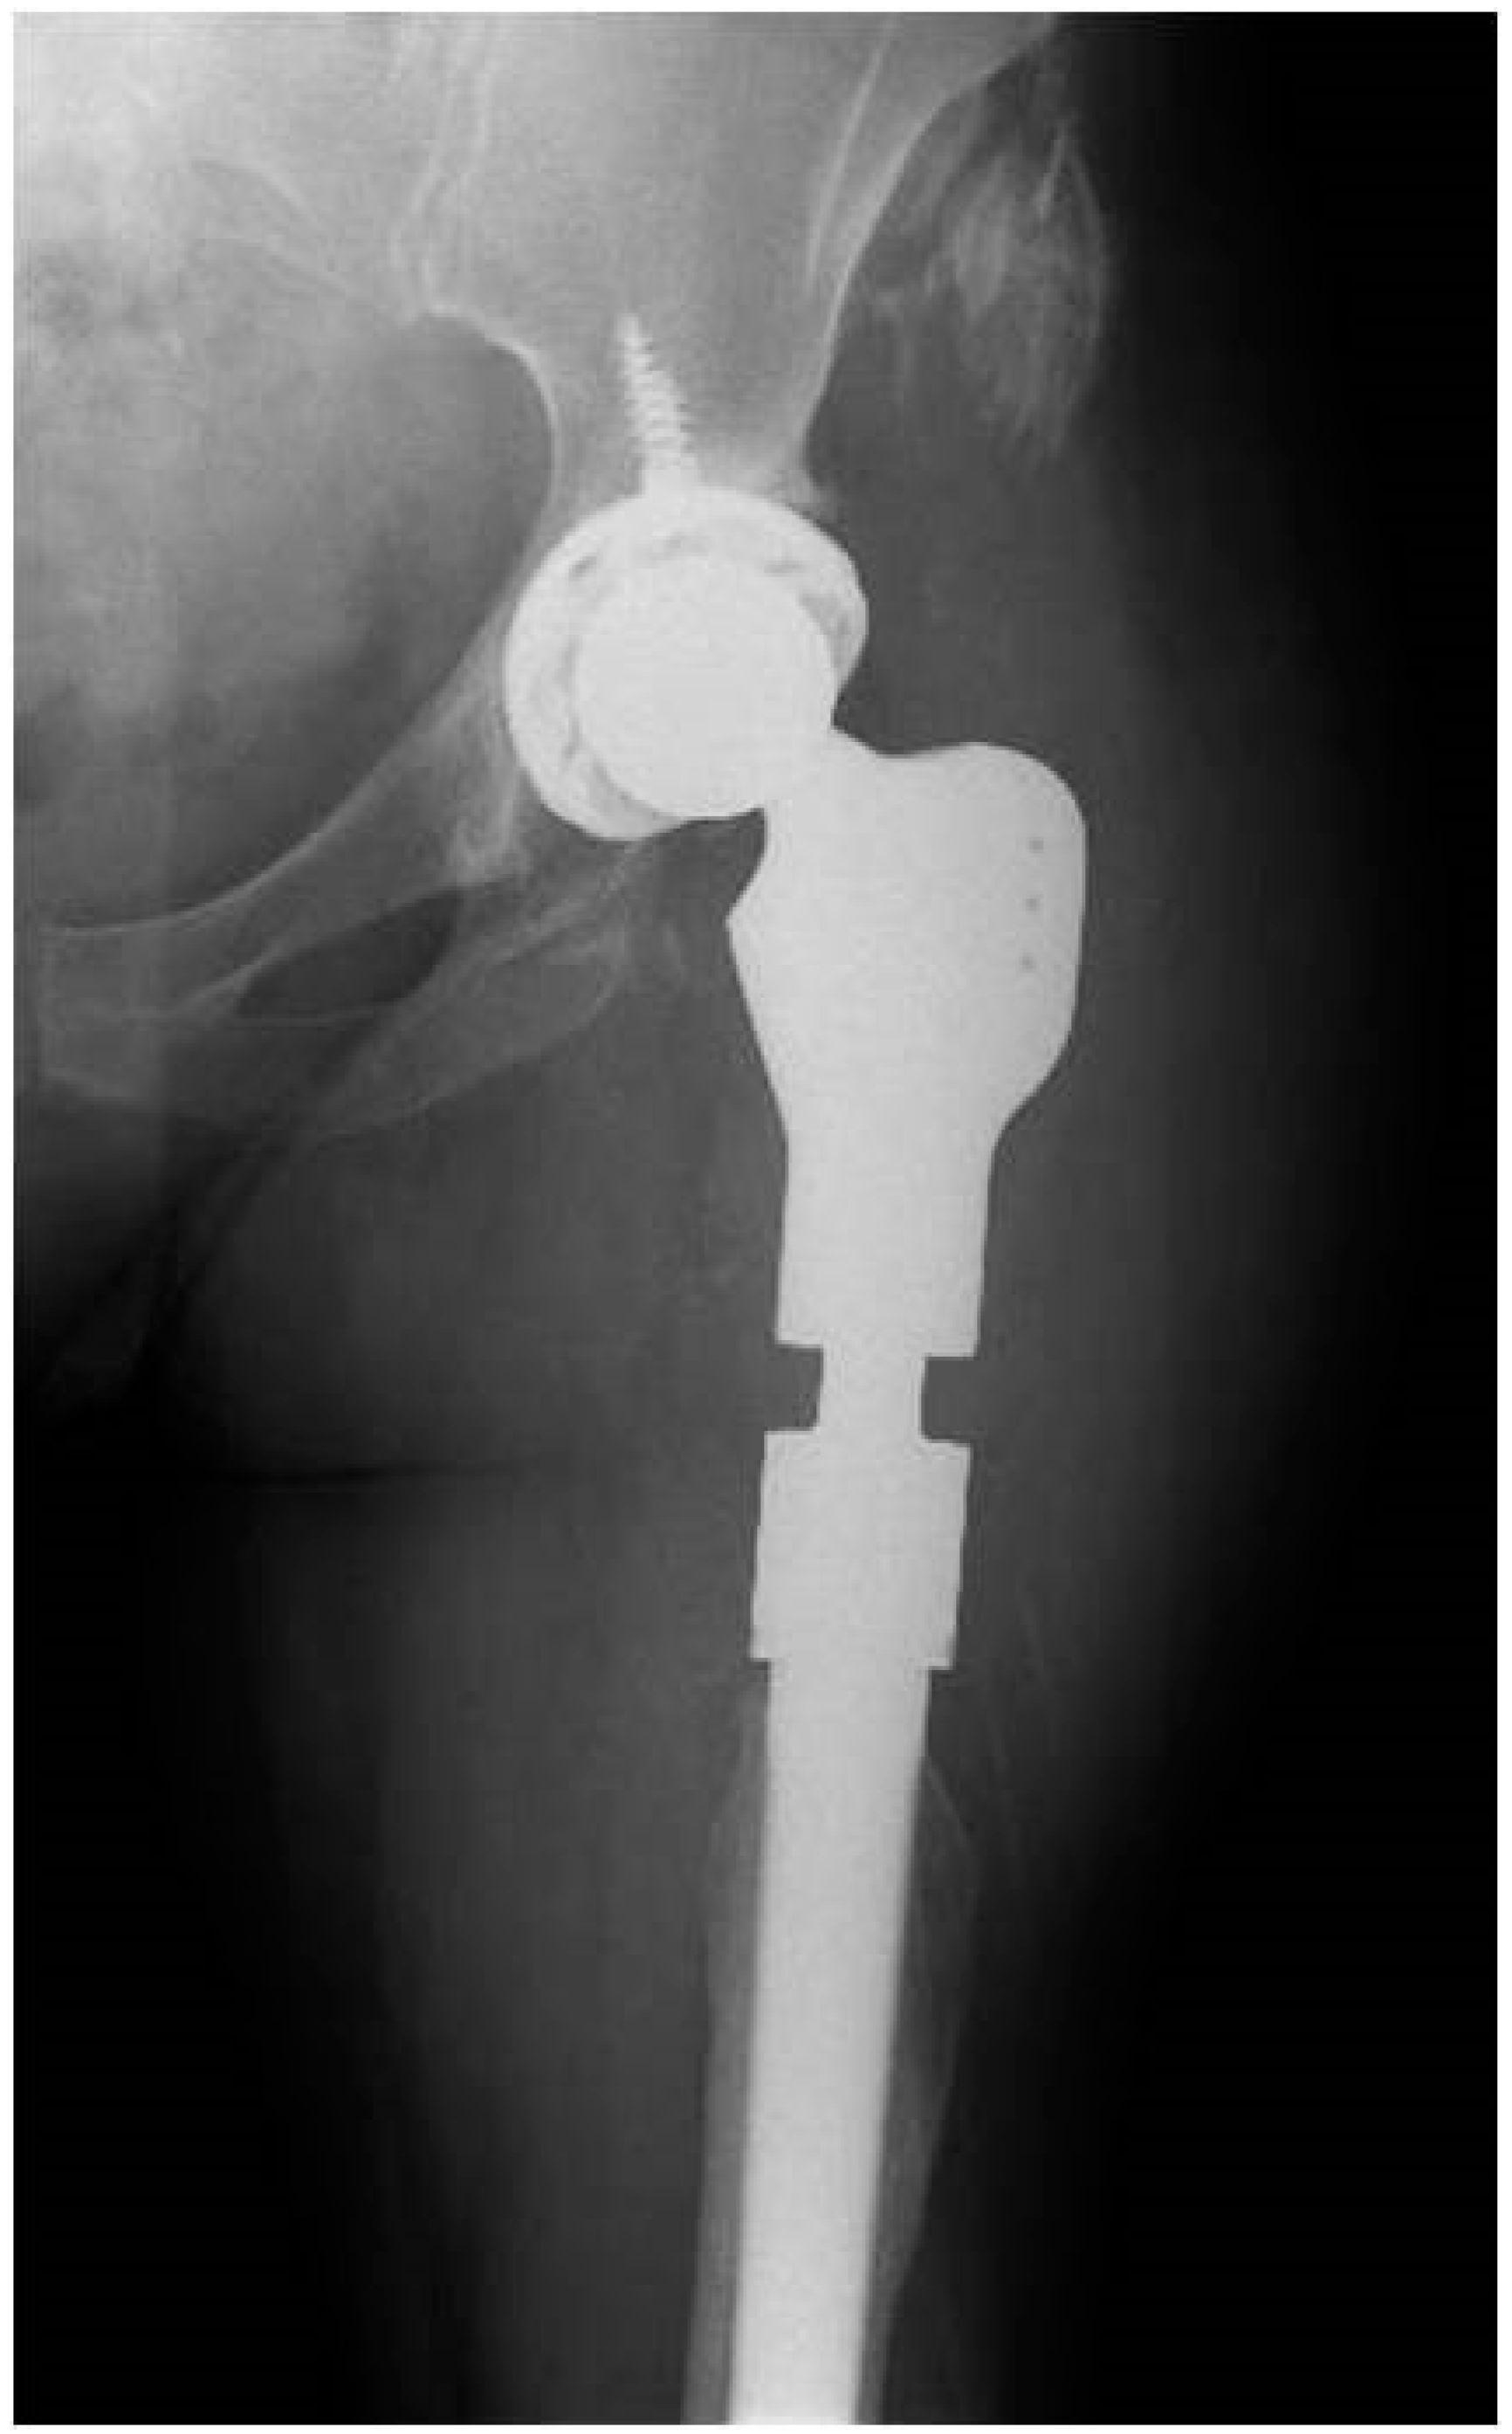

One-Stage Hip Revision Arthroplasty Using Megaprosthesis in Severe Bone Loss of The Proximal Femur Due to Radiological Diffuse Osteomyelitis

2.1. Case 1

2.2. Case 2